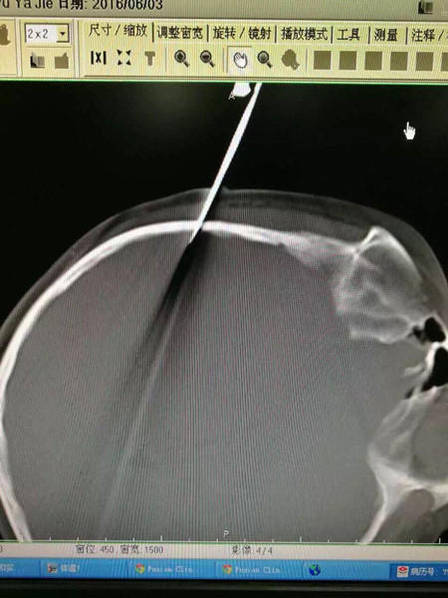

上海: 爸爸手一滑,剪刀插入女儿太阳穴(图/慎入)

6月4日消息,昨晚,上海交通大学附属新华医院收治了一名剪刀插头的女童。经过及时救治,目前这名10岁女童已经完全清醒,正在接受进一步治疗。而女童受伤竟是爸爸“吓唬一下”带来的意外。图为一把剪发用的剪刀从女孩头部右侧插入。

Continue Reading 上海: 爸爸手一滑,剪刀插入女儿太阳穴(图/慎入)